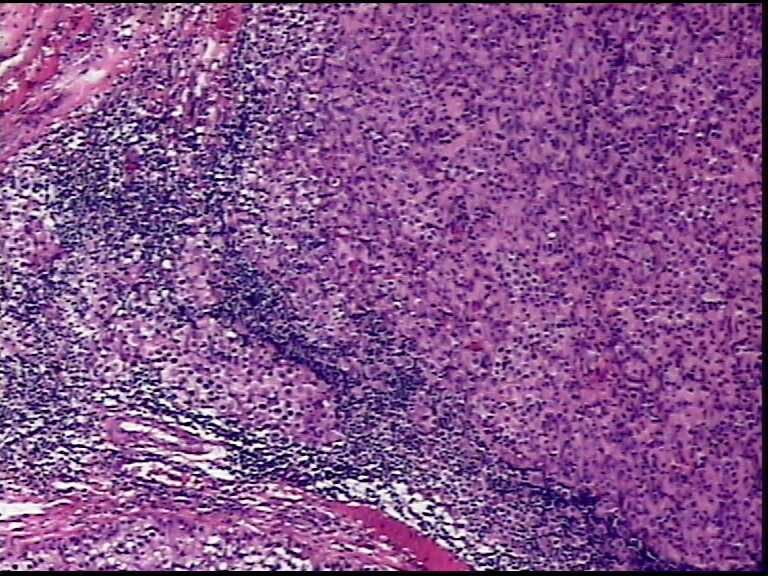

患者男性,34岁,临床没给提供,该患者梅毒阳性

• 请各位老师会诊一下 颌下淋巴结图3

图3

颌下淋巴结肿大,送检肿物直径2.5cm,切面灰粉色,质地嫩,先做了个LCA瘤细胞阴性

淋巴结内见大量宽而嗜酸性胞浆的肿瘤细胞,瘤细胞核大,偏心分布,核仁明显,成上皮样表现,部分似有腺泡样排列,符合淋巴结转移性恶性肿瘤,首先除外转移癌,恶性黑色素瘤,继而除外浆细胞瘤(岁数不太符合),横纹肌肿瘤等。

淋巴结内见大量宽而嗜酸性胞浆的肿瘤细胞,瘤细胞核大,偏心分布,核仁明显,成上皮样表现,部分似有腺泡样排列,符合淋巴结转移性恶性肿瘤,首先除外转移癌,恶性黑色素瘤,继而除外浆细胞瘤(岁数不太符合),横纹肌肿瘤等。同意楼上的观点。

有梅毒病史,还是把梅毒性淋巴结炎伴plasmocytosis排除后再考虑其它。